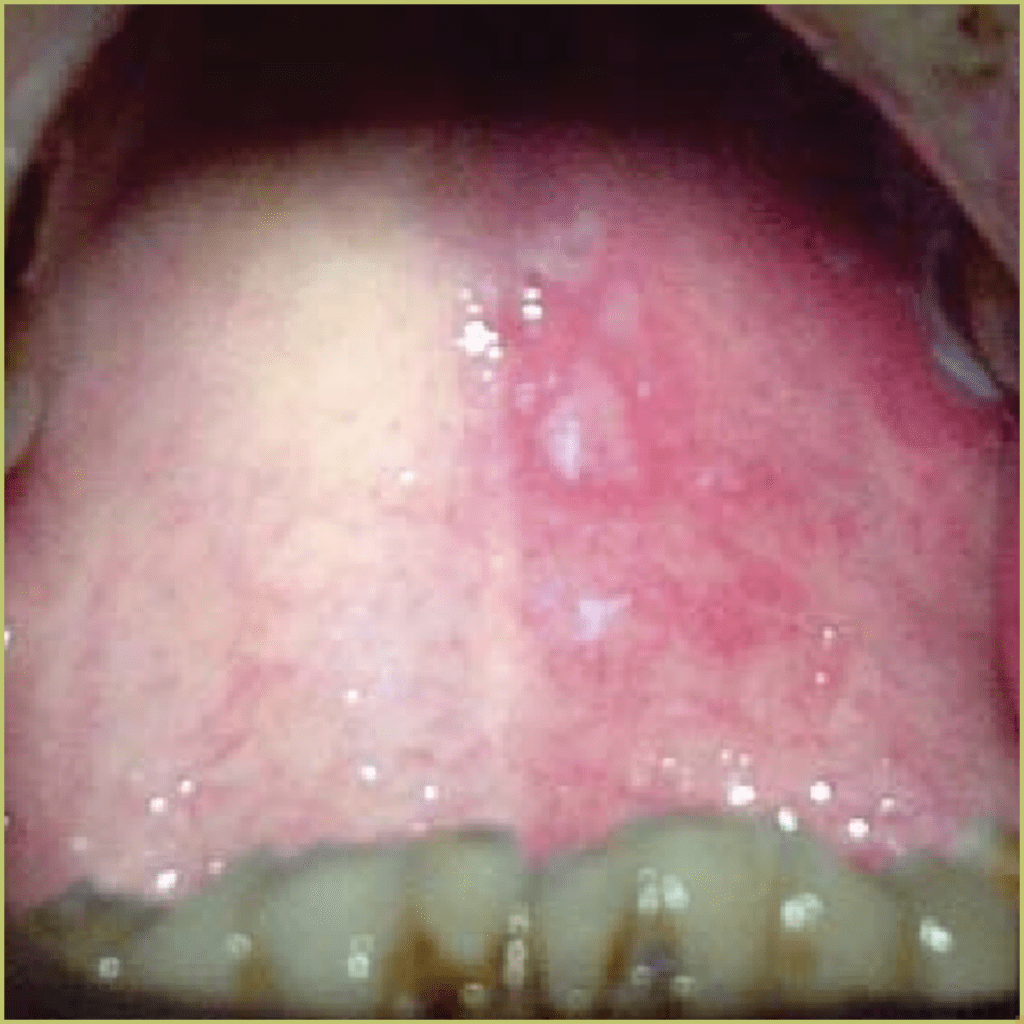

HERPANGINA

Herpangina is a highly contagious disease usually caused by a coxsackie (A and B) virus infection. Though primarily a pediatric disease it may present in newborns, adolescents, and young adult patients. The common clinical presentation includes

- Incubation period of 5 to 9 days, resolves within 2 weeks.

- Acute onset of symptoms that involves the posterior oral cavity.

- Macular erythematous areas precede short-lived vesicular eruption, followed by ulceration.

- Pharyngitis, dysphagia, fever, malaise, headache, and lymphadenitis.

Diagnosis is usually based on the lesion history and clinical presentation only. Your differential diagnosis should include:

- Hand-foot-and-mouth disease.

- Varicella (chicken pox).

- Acute herpetic gingivostomatitis.

The disease is self-limiting and treatment is usually palliative only.